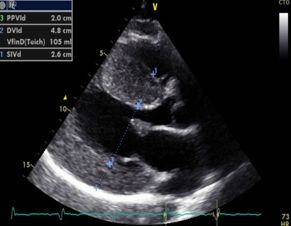

Adiestramiento en ecocardiografia( ultrasonido del corázón) en pacientes con cáncer .Utilizando técnicas avanzadas de mecánica ventricular. Donde se diagnóstica los efectos del tratamiento del cáncer en el corazón desde etapas muy tempranas antes de que se presenten los sintomas y se pueda otorgar tratamiento preventivo para cuidar el corazón.

Ecocardiograma transtoracico con el mejor equipo de la región

• Ecocardiografía